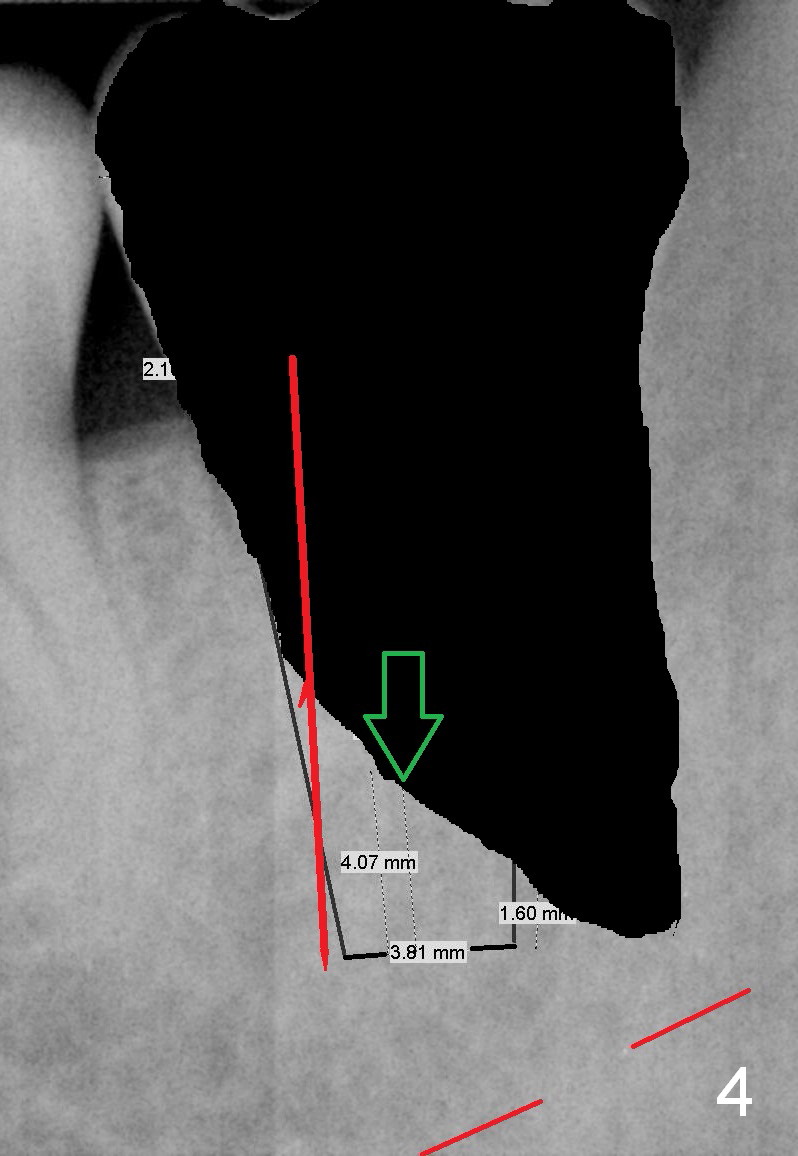

A 34-year-old man has distal deep caries of the lower 2nd molars. Root canal therapy turns out to be difficult on the right side due to bleach leakage. It would be also difficult to restore the distal defect. Finally he agrees to have extraction and implant. The result is good. He is ready to accept the same treatment for the left 2nd molar (Fig.1 (arrowheads: caries)). Metronidazole will be used for socket decontamination. Place a 5.9x10 mm bone-level implant 2 mm below the mesial crest (hopefully at the same level of the buccal crest) so that there is enough height to place an abutment (Fig.2). The apex of the implant is placed mesial to that of the root, since there is more bone, away from the superior border of the Inferior Alveolar Canal (red dashed line). The osteotomy is to be initiated in the middle of the mesial slope obliquely, more mesial (Fig.3 red line) than the center of the implant (green arrow). Once the lamina dura is penetrated, change the trajectory along the future long axis of the implant (Fig.4 red line). The depth will be 14 mm from the mesial gingival line (Fig.2). As the diameter of drills increases, the osteotomy tends to shift distal (Fig.5 pink arrow).